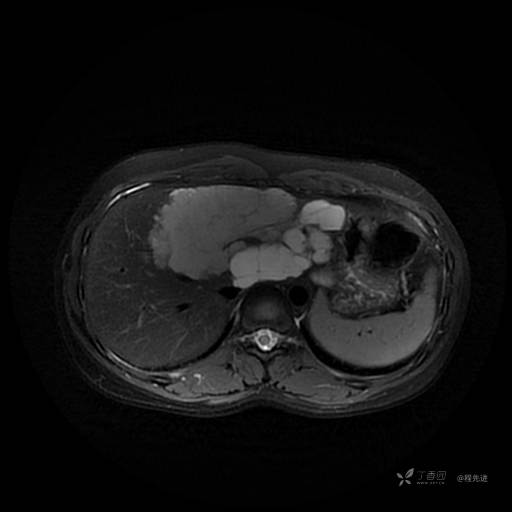

MR平扫+增强

每个序列一张图像(图像太多了,恕不一一发上来)